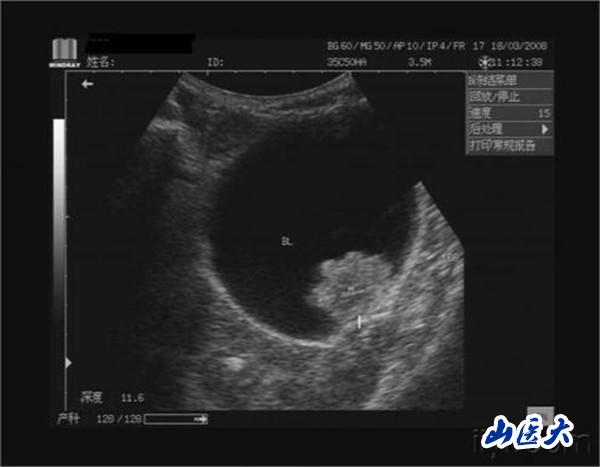

膀胱肿瘤是泌尿系统中最常见的肿瘤,多数为移行上皮细胞癌,在膀胱侧壁及后壁最多,其次为三角区和顶部。在国外,膀胱肿瘤的发病率在男性泌尿生殖器肿瘤中仅次于前列腺癌,居第2位,在国内则占首位。男性发病率为女性的3~4倍,年龄以50~70岁为多。非肌层浸润膀胱肿瘤(浅表性膀胱癌)占初发膀胱肿瘤的70%,治疗方法主要是手术切除。